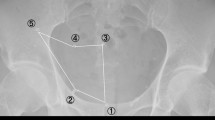

Surgical technique and intra-operative view. Operation on right side indirect hernia (EHS: P-L-1).